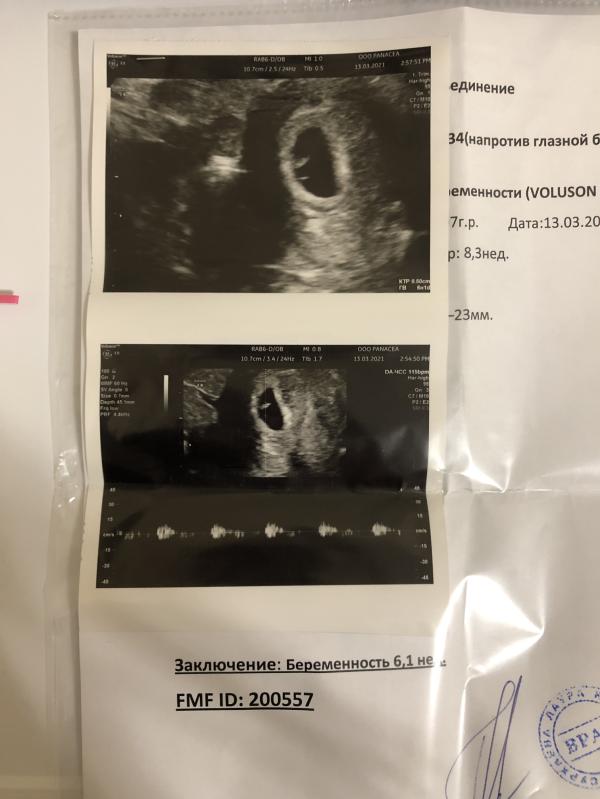

А если посмотреть пост от 26 числа то я писала, что встала на учёт к Джуме Хизрикадиевне , я немного скептична была настроена к ее этапам лечения. Я не собиралась вызывать менструацтю, не собиралась пить кок. И вот в очередной приём я пришла , она назначила анализы мне ,мы побеседовали. Я ушла. Шла пешком домой, прошла мимо аптеки и купила тесты. Мес не идут, цикл долгий, на всякий. И вот я опускаю тест, и не успев вытащить яркие/жирные/красивые две полоски!! Мой шок и мою радость опис...